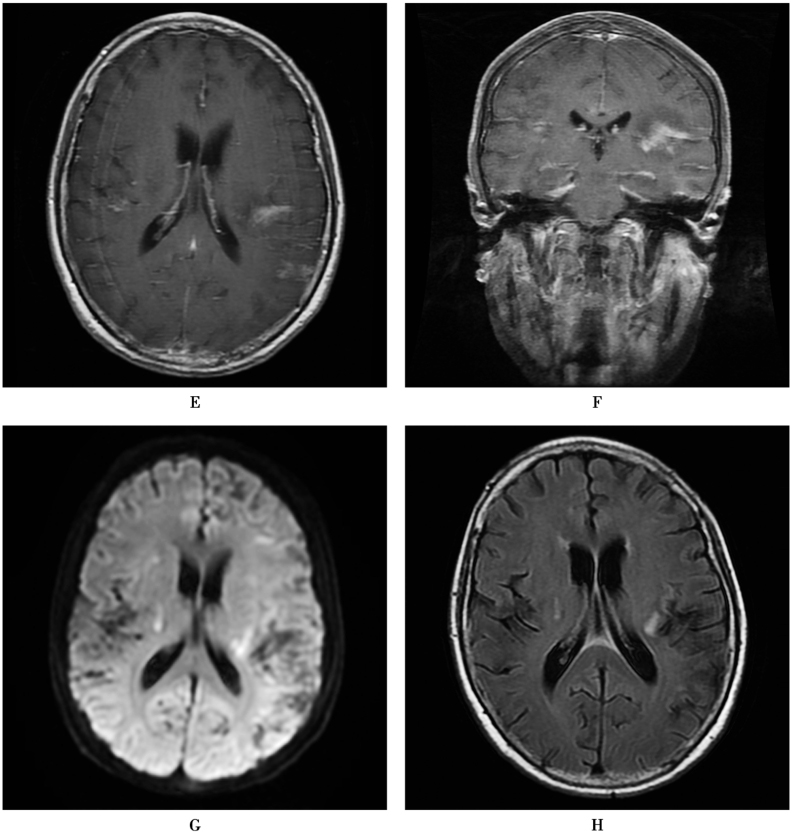

图1 化脓性脑膜炎

患者,女,62岁,发热2周,意识障碍5天。白细胞18.77×109/L,中性粒细胞百分比92.1%。血培养11小时报警:革兰氏阴性杆菌。脑脊液检查:“米汤”样,压力300mmH2O,白细胞154.61×106/L(多核86.8%),葡萄糖0.0mmol/L,氯化物108mmol/L,蛋白7.41g/L,抗酸染色(-)。随后血培养、脑脊液培养回报铜绿假单胞菌。既往史:中耳炎病史,中耳息肉切除术后。A.MRI显示右侧中耳乳突黏膜增厚,明显强化;B.脑桥周围软脑膜、小脑幕异常强化,提示炎症改变;C.幕上脑室扩张,双侧脑室后角内DWI高信号,提示积脓。D~F.1个月后复查,双侧基底节、小脑半球多发梗死灶;G、H.颅底、侧裂柔脑膜强化较前明显